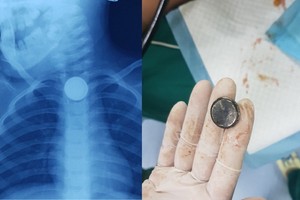

女童誤吞紐扣型電池致食管灼傷